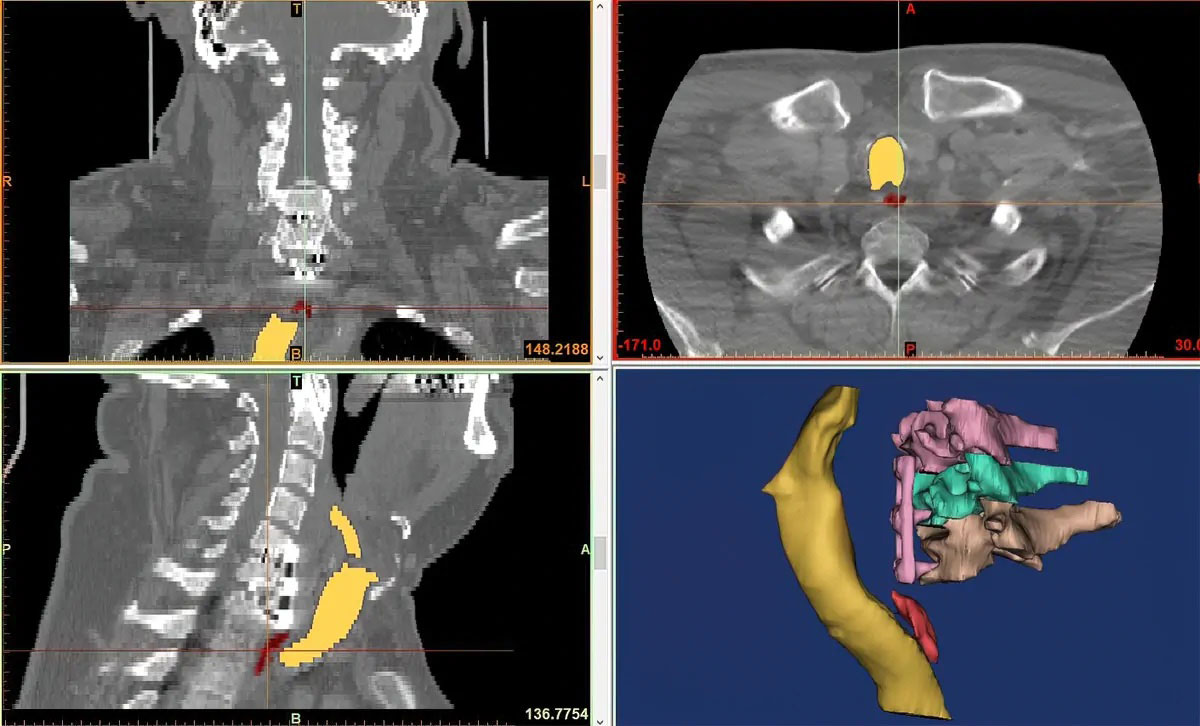

Malpractice suits are typically difficult to understand because of the medical jargon and body scans used as evidence. A courtroom exhibit effectively visualizes how surgery may have gone wrong or how a misdiagnosis caused harm to a patient. These medical courtroom exhibits are accurate because they are made directly from the data collected from diagnostic tests.

A high-resolution CT or MRI scan provides internal images of a person and when broken down, these images, layer-by-layer, create a precise anatomical replica. Replicas of abnormalities such as tumors, fractures, cysts, and the like have staggering accuracy. WhiteClouds, approached by prosecuting and defense attorneys alike, creates true-to-life medical exhibits for use in the courtroom.

An attorney approached WhiteClouds to create a courtroom exhibit highlighting an area of his client’s spine. The client had undergone a surgery where the surgeon improperly attached hardware to his cervical spine. The surgical mistake caused the medical device to dig into the man’s esophagus. A trained medical professional could see the resulting damage in the medical imagery, but it was difficult for the attorney to get the jury to understand what the experts could. The true-to-life exhibit, created by WhiteClouds, brought a more in-depth understanding to the courtroom.